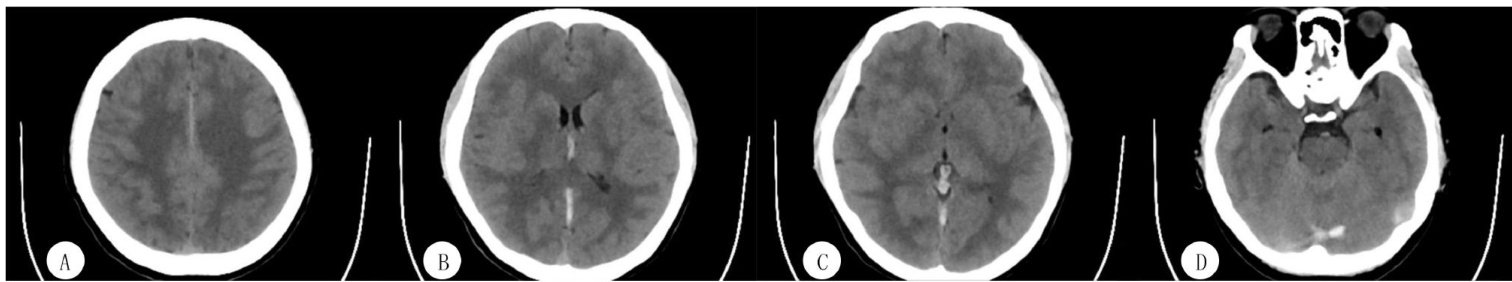

抗磷脂综合征致青年静脉窦血栓1例并文献复习

[Abstract]ObjectiveToexplorethediagnosisandtreatment strategiesforantiphospholipidsyndrome-induced venous sinus thrombosis ina young adult.MethodsAcaseof venous sinus thrombosis caused byantiphospholipid syndromeinayoungadult was reported.Thediagnosisand treatment processof thispatientandrelatedliterature werereviewed.ResultsThepatient,a young female,wasadmitedtohospitalwithcomplaintsofheadacheand was diagnosed with venoussinus thrombosis.Common causes wereexcludedandantiphospholipidsyndromewasconfirmedastheunderlying etiology.The patientshowed improvement andwasdischargedafteranticoagulationtherapy,withfolow-upindicatingsignificantresolutionofthevenoussinusthrombosis. ConclusionAntiphospholipidsyndromecombinedwithintracranialvenous sinus thrombosis isararebutserious disease,which canlead tointracranialhypertensioandvenouscerebralinfrctionEarlydiagnosisandlong-termstandardizedanticoagulantthrapy can improve the prognosis of such patients.

抗磷脂综合征(APS)是一种具有特异性临床病理表现的凝血原性自身免疫性疾病,是引起急性缺血性卒中和短暂性脑缺血发作(TIA)的明确原因,特别是在年轻病人中[1]。(剩余9036字)